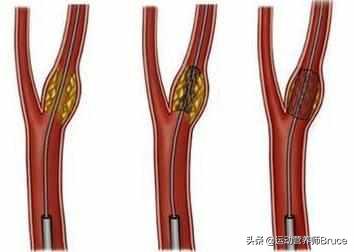

Sous l'influence de facteurs de risque cardiovasculaire tels que l'hyperlipidémie, la paroi interne des vaisseaux sanguins est progressivement endommagée et les lipides en excès dans le sang se déposent progressivement sous la paroi du vaisseau, formant un noyau lipidique athéromateux jaune, et finalement une chape fibreuse se forme dans le noyau lipidique, ce qui constitue le processus de formation de la plaque artérielle. La plaque est un facteur de risque conduisant à l'athérosclérose, et les plaques qui ont des problèmes de stabilité et se rompent peuvent conduire à une agrégation plaquettaire réactive. L'agrégation réactive des plaquettes peut même conduire à la formation de caillots sanguins, bloquant les vaisseaux artériels et provoquant des maladies cardiovasculaires infarciques. Ce qu'il faut faire, c'est prévenir la formation de la plaque par des médicaments et des exercices raisonnables, essayer de maintenir la stabilité de la plaque existante, ralentir le processus d'athérosclérose et empêcher la rupture de la plaque d'entraîner un risque plus élevé.

La plaque a la plaque veineuse, la plaque artérielle, c'est dans le rôle de multiples facteurs étiologiques, en raison de la lipidation de la précipitation, pour dire les choses franchement, c'est-à-dire, vous graissez plus, la digestion et l'utilisation ne peut pas être, dans les lipides sanguins quatre et d'autres facteurs multiples sous l'influence de et puis des dommages à l'intima, le dépôt à la couche interne des vaisseaux sanguins, la formation d'un noyau lipidique jaune athéromateux, et finalement dans la formation d'un noyau fibreux sur le noyau lipidique, qui est normalement très stable, si la coiffe fibreuse est soumise à une inflammation soutenue. la chape fibreuse se rompt, la plaque s'écoule et les plaquettes sanguines dans le mariage éclair donnent naissance à un enfant perturbateur, appelé thrombus, qui se promène pour semer le trouble, se spécialise dans les mauvaises actions pour bloquer les vaisseaux sanguins, le thrombus dans la lumière des vaisseaux sanguins devient plus étroit en même temps, mais aussi se rompt, déclenchant des événements vasculaires cardio-cérébraux et cérébraux aigus, tels que l'accident vasculaire cérébral, l'infarctus du myocarde, l'embolie pulmonaire, l'insuffisance rénale, les veines variqueuses, etc. etc. Par conséquent, l'élimination de la plaque ne permet pas seulement de déboucher les vaisseaux sanguins, mais aussi de prévenir les accidents cardiovasculaires et cérébrovasculaires aigus, ce qui est dans l'esprit de tout le monde.

La plaque artérielle est une série de réactions inflammatoires déclenchées par des lésions de la paroi artérielle sous l'effet de multiples facteurs étiologiques, avec la formation ultérieure d'une plaque athéromateuse secondaire. La formation de la plaque est plus nocive pour le corps humain, elle rétrécit la lumière du vaisseau sanguin en même temps, elle peut aussi se rompre, déclenchant des événements cardiovasculaires aigus, par conséquent, l'élimination de la plaque non seulement débouche le vaisseau sanguin, mais prévient également les événements cardiovasculaires aigus, qui sont le battement de cœur de tous les patients. Pour le traitement de la plaque, nous pouvons commencer par la cause de la maladie, comme le contrôle des lipides sanguins, de la tension artérielle, de la glycémie, etc., ainsi que le changement d'un mauvais mode de vie, comme un régime pauvre en sel et en cholestérol, l'augmentation de l'exercice, l'arrêt du tabac et la limitation de l'alcool, etc. ou, en plus du traitement ci-dessus, nous pouvons donner des médicaments, et le choix du médicament est la statine, comme l'atorvastatine, la reserpulvastatine et ainsi de suite sont couramment utilisés dans le traitement des plaques d'athérome, et le choix exact du traitement doit être formulé sous la direction d'un médecin spécialiste. Le choix exact du traitement doit être formulé sous la direction d'un médecin spécialiste. Le plan de traitement spécifique doit être formulé sous la direction de médecins spécialistes.

Le processus de formation de la plaque passe par plusieurs étapes : tout d'abord, l'endothélium du vaisseau sanguin est endommagé, comme si la couche protectrice de la surface interne du vaisseau sanguin était "brisée" ; les macromolécules de graisses présentes dans le sang sont transportées par une sorte de substance appelée lipoprotéine de basse densité dans la couche intima-média de la paroi du vaisseau sanguin, où elles s'accumulent en grandes quantités ; la paroi du vaisseau sanguin s'épaissit et le traitement médical consiste à épaissir la couche intima-média de plus d'un millimètre, ce qui est considéré comme de l'athérosclérose. Lorsque l'épaississement de la couche intima-média dépasse 1 mm, on parle d'athérosclérose, telle que l'agrégation locale en une masse, c'est-à-dire la plaque précoce.

Au début de la formation de la plaque, l'accumulation de graisse provoque une série de réactions inflammatoires ; en fait, la graisse est constamment oxydée, dénaturée et forme des substances ressemblant à de la bouillie ; ces substances détruisent la structure normale des vaisseaux sanguins et deviennent partie intégrante des vaisseaux sanguins ; à ce moment-là, la matière lipidique est principalement à l'état liquide, ce que l'on appelle généralement des taches molles.

La matière lipidique d'un point faible peut se nécroser avec le temps, tout comme une infection cutanée devient fibrotique et croûteuse lorsqu'elle se remplit de pus, ou la calcification se produit lorsqu'il y a des dépôts de calcium, que la plaque se durcit et que la fonction vasoconstrictrice des vaisseaux sanguins est davantage compromise ; ces plaques sont appelées des points durs.

Les plaques précoces peuvent ne pas avoir gravement endommagé la structure des vaisseaux sanguins et il est possible qu'elles puissent être éliminées et inversées, tandis que les plaques molles et les plaques dures ont déjà remplacé la structure normale des vaisseaux sanguins. Il est impossible de les éliminer complètement, et ce qu'il faut faire, c'est arrêter et ralentir la croissance continue des plaques.